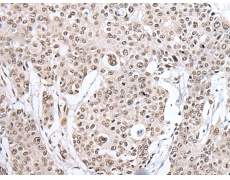

IHC positive control:

Human esophagus cancer and human liver cancer

IHC Recommend dilution:

25-100